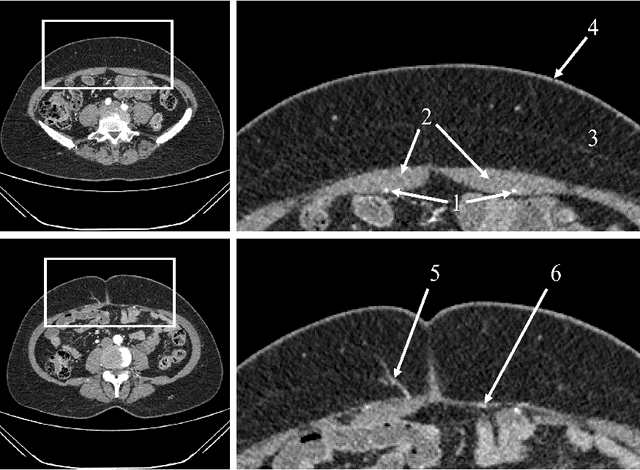

Abstract:The deep inferior epigastric artery perforator (DIEAP) flap is the most common free flap used for breast reconstruction after a mastectomy. It makes use of the skin and fat of the lower abdomen to build a new breast mound either at the same time of the mastectomy or in a second surgery. This operation requires preoperative imaging studies to evaluate the branches - the perforators - that irrigate the tissue that will be used to reconstruct the breast mound. These branches will support tissue viability after the microsurgical ligation of the inferior epigastric vessels to the receptor vessels in the thorax. Usually through a Computed Tomography Angiography (CTA), each perforator, diameter and direction is manually identified by the imaging team, who will subsequently draw a map for the identification of the best vascular support for the reconstruction. In the current work we propose a semi-automatic methodology that aims at reducing the time and subjectivity inherent to the manual annotation. In 21 CTAs from patients proposed for breast reconstruction with DIEAP flaps, the subcutaneous region of each perforator was extracted, by means of a tracking procedure, whereas the intramuscular portion was detected through a minimum cost approach. Both were subsequently compared with the radiologist manual annotation. Results showed that the semi-automatic procedure was able to correctly detect the course of the DIEAPs with a minimum error (average error of 0.64 mm and 0.50 mm regarding the extraction of subcutaneous and intramuscular paths, respectively). The objective methodology is a promising tool in the automatic detection of perforators in CTA and can contribute to spare human resources and reduce subjectivity in the aforementioned task.